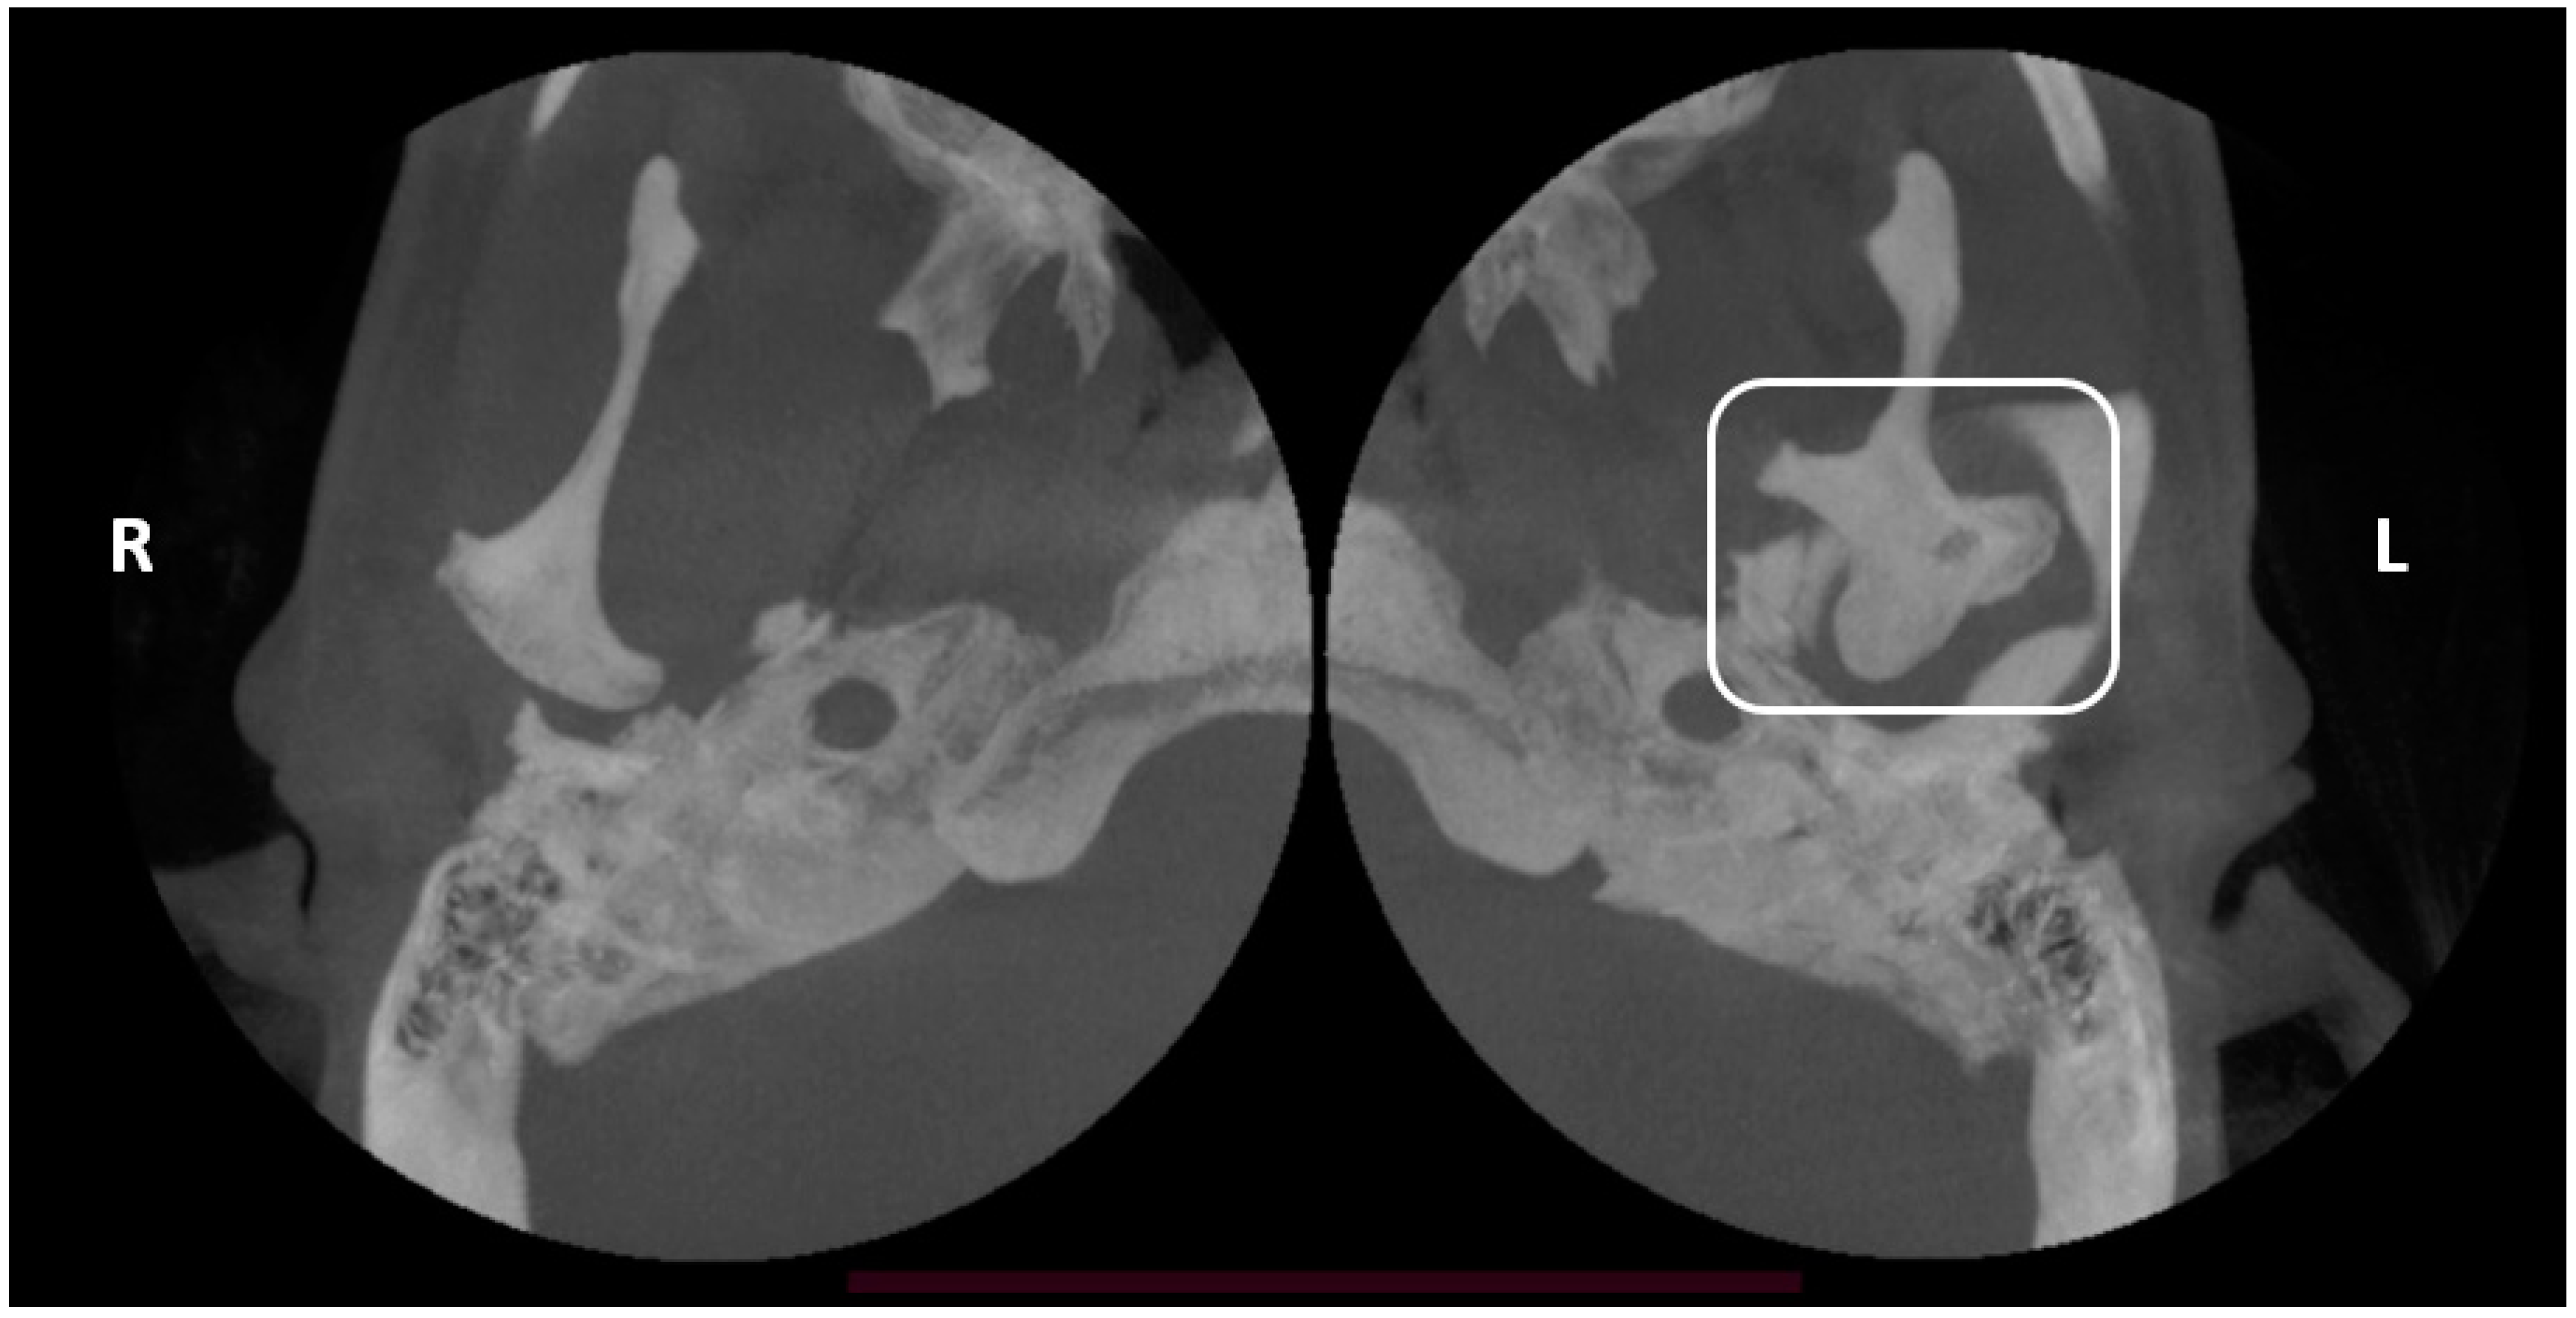

| Sezgin & Katipman 2009 [3] | M, 31 | Mandible deviated to the right | Trauma | FU | - |

| Prasanna T. et al., 2015 [1] | F, 26 | Mild facial asymmetry, micrognathia & deviation of the mandible to left | - | None | - |

| Hernández-Andara A. et al., 2017 [8] | M, 12 | Facial asymmetry & a clicking noise in the left TMJ | Trauma | FU | - |